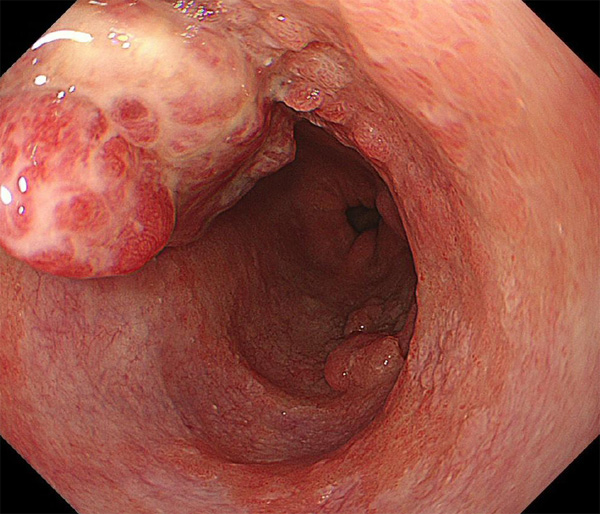

内視鏡所見と病理組織像の1対1対応が可能な症例を公募いたします。主にLSBEに発生した早期癌(HGDを含む)を対象としますが、興味深い症例であればSSBE癌でも結構です。採否は世話人へご一任ください。

症例呈示希望者は応募用紙に記入の上、代表的な内視鏡(2枚)、切除標本(新鮮、固定)、切り出し図、マッピング、代表的組織像とともに、Barrett 食道研究会事務局 barrett.shinshu@gmail.comへお申し込み下さい(10MB以下でお願い致します)。

特に、本邦では極めて稀なlong segment Barrett’s esophagus(LSBE)から発生した早期癌は、診断に難渋する場合も多く、欧米ではランダム生検による検出が標準的とされています。背景のBarrett食道もろとも全体を内視鏡切除+ラジオ波焼灼する欧米と異なり、ESDで内視鏡的な局所切除が基本の本邦では、存在診断+範囲診断(特に水平)を的確に行うことが不可欠です。

そのためには、一流の病理医による組織学的診断とエキスパート内視鏡医による拡大内視鏡像との一対一対応を徹底的に行うことで、『本来、見えないであろう拡大所見の先にある組織構築像が診えてくる』所まで内視鏡診断レベルを上げていく必要があります。その実現には、一対一対応を追究した症例(特にLSBE発生例)1例でも多く経験するしかありません。本研究会でBarrett食道腺癌(LSBE発生早期病変)を共に学び、拡大内視鏡像の一歩先を診るスキルを習得しましょう!一人でも多くの皆様のご参加をお待ちしています。

2026年1月24日開催の第19回研究会でご提示した検討症例です。 (画像をクリックすると拡大します)